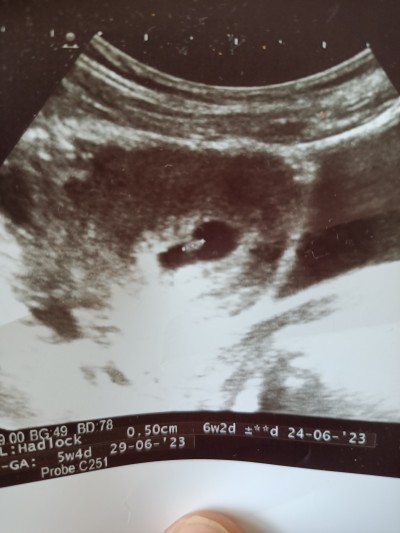

Önceki paylaismimda küçüktü şimdi kalp atışlarını duydum bu yeni resmimiz şimdi tahmin edersiniz cinsiyeti :)

6haftalik burda tabi canım doktorlar bile yaniliyo cinsiyette ama eğlencesine koydum bende tutacakmi diye merak ettim çok fazla böyle soru var cunku